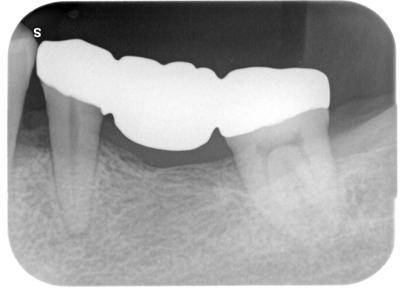

術前

多田_直樹_ライトボックス(1)_口腔内_20210610_182248.jpg

◯内の骨が凹でいる。

歯周ポケット数値も5mmくらいある。(正常0〜3mm)

歯周病の進行。

状況は厳しいが、この歯がなくなると、部分義歯もしくはインプラントとなるので何とか残したい。

患者さんは抜歯してインプラントを希望されたが、歯科医として、そこは歯牙を残してナンボ。

通常のスケーリング、ルートプレーニングを行い、一定の改善は見られたが、歯周外科治療行う事によりさらなる改善を目指す。